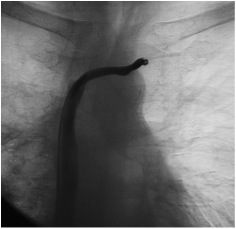

Recanalização de veias torácicas

Existem situações em que ocorre obstução total das veias braquiocefálicas, que são as veias que drenagem o sangue dos membros superiores de volta para o coração. Isso se deve, na maioria das vezes, por repetidas cateterizações destas veias, sobretudo nos pacientes mais graves de UTI ou naqueles que necessitam de cateteres para hemodiálise.

Atualmente, a recanalização destes vasos ocluídos por técnica endovascular é a única opção de tratamento. Estes procedimento podem ser realizadas com anestesia local, através de punção das veias centrais – sem a necessidade de cortes – utilizando-se cateteres que possuem balões de dilatação na sua ponta com ou sem o uso se stents.